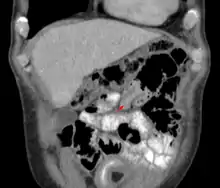

| An intussusception as seen on CT | |

The cause in children is typically unknown; in adults a lead point is sometimes present.[1] Risk factors in children include certain infections, diseases like cystic fibrosis, and intestinal polyps.[1] Risk factors in adults include endometriosis, bowel adhesions, and intestinal tumors.[1] Diagnosis is often supported by medical imaging.[1] In children, ultrasound is preferred while in adults a CT scan is preferred.[1]

An intussusception is often suspected based on history and physical exam, including observation of Dance's sign. A digital rectal examination is particularly helpful in children, as part of the intussusceptum may be felt by the finger. A definite diagnosis often requires confirmation by diagnostic imaging modalities. Ultrasound is the imaging modality of choice for diagnosis and exclusion of intussusception, due to its high accuracy and lack of radiation. The appearance of target sign (also called "doughnut sign" on a sonograph, usually around 3 cm in diameter, confirms the diagnosis. The image seen on transverse sonography or computed tomography is that of a doughnut shape, created by the hyperechoic central core of bowel and mesentery surrounded by the hypoechoic outer edematous bowel.[11] In longitudinal imaging, intussusception resembles a sandwich.[11] It is also called "pseudokidney" sign because hyperechoic tubular centre is covered by a hypoechoic rim producing a kidney-like appearance.[12]